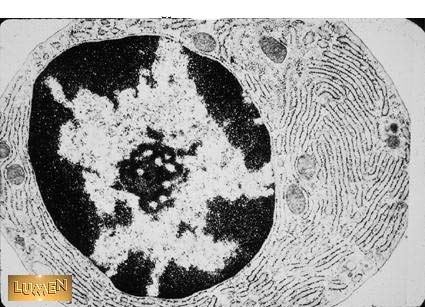

What kind of cell is this and what does it produce?

Answer

Plasma cell - antibodies